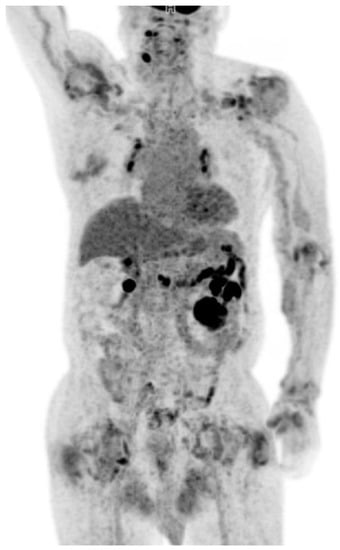

Visualization of Dialysis-Related Amyloid Arthropathy on 18F-FDG PET-CT Scan

Cheon, M.; Yoo, J. Visualization of Dialysis-Related Amyloid Arthropathy on 18F-FDG PET-CT Scan. Diagnostics 2022, 12, 113. https://doi.org/10.3390/diagnostics12010113